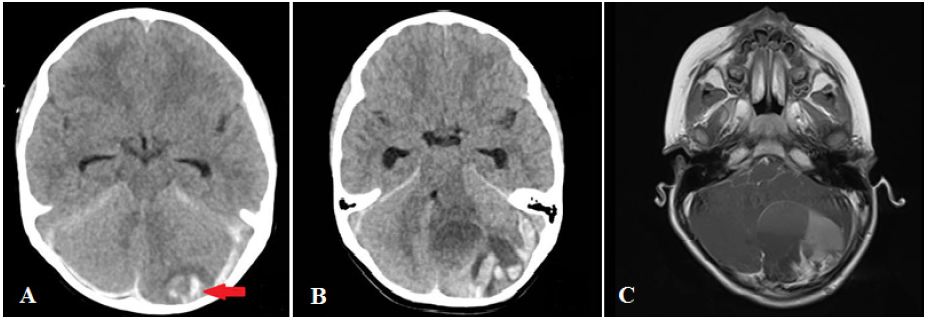

Paciente mujer de 4 años ingresó a emergencia en octubre del 2020 por presentar cefalea y náuseas tras haberse caído de cama aparentemente, no hubo pérdida de conciencia. Al examen físico, la paciente presentaba palidez, somnolencia, pupilas isocóricas, fotorreactivas, con puntaje en la ECG de 13, sin déficit motor. Se realizó tomografía cerebral sin contraste donde se evidenció un pequeño sangrado periférico en el hemisferio cerebeloso izquierdo sin efecto de masa. Esta imagen fue descrita como contusión hemorrágica cerebelosa izquierda (figura 2A). Paciente ingresó a la Unidad de Cuidados Intensivos Pediátricos para monitoreo neurológico. Paciente evolucionó sin complicaciones, siendo dada de alta a los dos días. Durante control por teleconsulta, se informó que la paciente había presentado cefalea y dolor cervical sin vómitos ni deterioro del sensorio, por este motivo se incrementó la dosis de analgésicos. Dos semanas después de ese control, la paciente volvió a emergencia por presentar cefalea súbita, un vómito y deterioro marcado del sensorio. Al examen físico, paciente se encontraba en sopor, presentando crisis epiléptica. Se tuvo que proceder a la intubación orotraqueal. En la tomografía cerebral sin contraste se evidenció una lesión de densidad heterogénea en hemisferio cerebeloso izquierdo, con sangrado asociado e importante efecto de masa que producía cierre del cuarto ventrículo y dilatación ventricular secundaria (figura 2B). Se realizó resonancia magnética cerebral donde se evidenció un proceso expansivo con componente hemorrágico, captador de contraste, localizado en el hemisferio cerebeloso izquierdo (figura 2C). Ante estado clínico del paciente se decidió intervenir quirúrgicamente de emergencia; se realizó una craneotomía suboccipital más resección de tumor cerebeloso, con colocación de drenaje ventricular externo occipital derecho. Se encontró en el acto operatorio un tumor grisáceo sangrante con pobre plano de clivaje y hematoma intraparenquimal asociado. Se realizó una resección quirúrgica amplia del tumor. No hubo complicaciones intraoperatorias. Después de la cirugía, la paciente evolucionó favorablemente, recuperando plenamente el estado de sensorio. Se retiró el drenaje ventricular externo tras comprobarse no hidrocefalia tras cierre de drenaje por más de 24 horas. La muestra tumoral fue informada por patología como sarcoma pleomórfico indiferenciado intracraneal primario con la siguiente inmunohistoquímica: PGFA negativo, desmina positivo focal, miogenina negativo, CD34 negativo, actina positivo focal, pérdida parcial ATRX, p53 positivo y sobre-expresado, OLIG-2 negativo. Con el diagnóstico histológico se activó el seguro oncológico particular del paciente siendo transferida a otra institución privada de salud a pedido de la familia para recibir quimioterapia y radioterapia.

A: Corte axial de tomografía cerebral de ingreso muestra aparente contusión hemorrágica cerebelosa izquierda (flecha roja) y sangrado tentorial. B: corte axial de tomografía cerebral sin contraste tras reingreso de paciente muestra masa de densidad heterogénea en hemisferio cerebeloso izquierdo con componente hemorrágico asociado a dilatación de cuernos temporales. C: corte axial de resonancia magnética cerebral con contraste donde se observa lesión captadora de contraste en hemisferio cerebeloso izquierdo que cierra cuarto ventrículo, compatible con un proceso expansivo con componente hemorrágico.